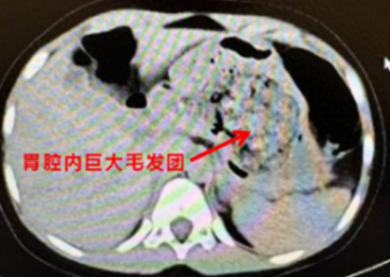

医生听到这里豁然开朗,原来在ct阅片的时候,发现了孩子胃里面有一团密度较高的团块,结合母亲提供的病史,医生断定孩子长期吃头发导致了胃内毛发成团,这也是这次腹痛的原因。

胃里巨大的毛发团

得出了初步诊断后,医生立即安排孩子住院,联系消化内科医生做胃镜检查,如果能够明确诊断,可以先尝试胃镜下取出,达到“无创”的效果。结果,当胃镜进入的瞬间,所有人都惊呆了,孩子胃内的毛发包裹食物残渣形成了一个巨大的团块,充满整个胃腔。